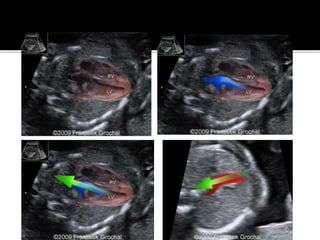

Using color Doppler ultrasound to access normal blood

flow. A, Color Doppler ultrasound shows

normal flow through the pulmonary artery (PA).

Color Doppler ultrasound to access normal blood flow through the aortic

arch (AA)

and descending aorta (D). Note that flow is continuous through the

descending aorta, but due to angle of 0 degrees in the middle of the

image, an artifact gives the appearance of narrowing, and the color of

flow changes from red to bluE